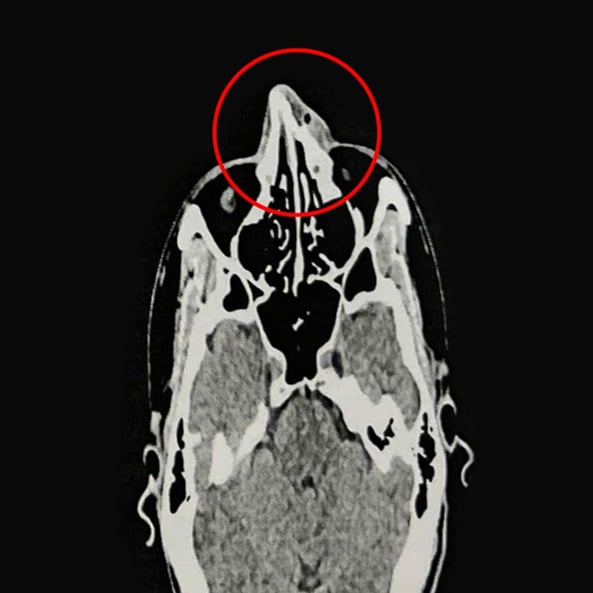

ThS.BS.CKI Nguyễn Trung Nguyên, Trung tâm Tai Mũi Họng, Bệnh viện Đa khoa Tâm Anh TP.HCM, cho biết kết quả nội soi và chụp CT 128 lát cắt ghi nhận xương mũi của anh Phi bị gãy ở vị trí tháp mũi, phù nề tụ khí mô mềm vùng mũi, lệch vách ngăn mũi, viêm mũi xuất tiết. Anh Phi được chỉ định phẫu thuật nâng xương mũi, chỉnh hình vách ngăn mũi.

Anh Phi được điều trị nội khoa ba ngày để giảm phù nề, mũi hết sưng viêm trước khi nhập viện phẫu thuật. Người bệnh được gây mê toàn thân. Qua nội soi kết hợp CT, bác sĩ Nguyên thấy mũi biến dạng, gãy di lệch tháp mũi và ngành lên xương hàm hai bên. Bác sĩ tiến hành chỉnh hình vách ngăn mũi, rạch niêm mạc vách ngăn phải bị vẹo, tách phần sụn tứ giác và phần xương vách ngăn bị vẹo, cắt bỏ phần xương, sụn vẹo. Sau đó nâng xương chính mũi và ngành lên xương hàm hai bên, chỉnh xương mũi thẳng, cân đối. Cuối cùng, bác sĩ đặt gạc meche chặt vào hốc mũi qua cửa mũi trước, cố định xương mũi đã nâng.